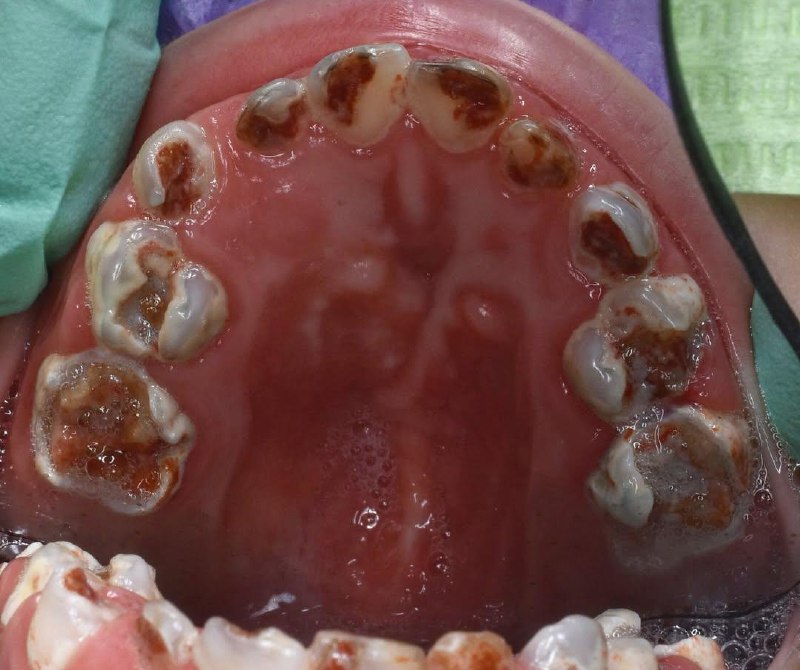

✨Вот как эндо выглядит в конце дня🐒 Автор Ahmed Ismail

10 мар. 2026 г.

7.3k 55 70